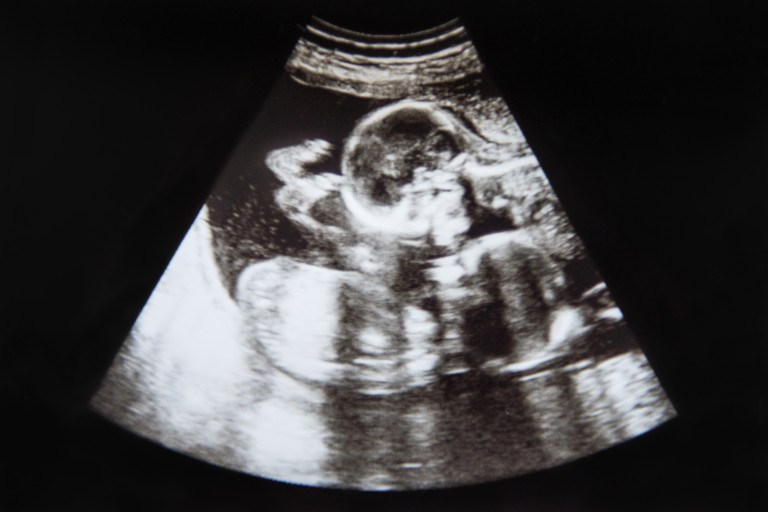

Проведено е най-мащабното изследване за въздействието на брата близнак върху живота на сестра му. Според резултатите от него, дамите, които са споделяли утробата на майка си с брат близнак е с 15,2% по-вероятно да не завършат гимназия, с 3,9% по-вероятно да не завършат висше обучение и с 11,7% по-вероятно да не се омъжат. И това не е всичко - те печелят с 8,6% по-малко, безработицата измежду тях е с 3,2% по-висока и раждат с 5,8% по-малко деца.

Данните за това изследване се основават на 728 842 раждания, в това число 13 800 близнаци в Норвегия, сред 1967 и 1978 година Взети са поради и други фактори, като месец и година на раждане, обучение на майката, възрастта ѝ по време на раждането и тежестта на бебето.

Изследването наблюдава 30 години от живота на близнаците - от раждането, през израстването до съзряването и демонстрира, че братът близнак оказва доста въздействие върху сестра си. Учените допускат, че това се дължи на обстоятелството, че момичето е било изложено на повишени равнища на тестостерон в продължение на толкоз дълго време.

Друга причина можело да бъде израстването с брат близнак, т.е. причина, която не е физиологична. Но откривателите открили, че същите зависимости се следят и при девойките, чиито братя близнаци са умряли скоро след раждането или в границите на една година след него. Това демонстрира, че повода се крие някъде в интервала преди близнаците да се родят.